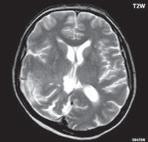

Obr. I.1.1h Fyziologický nález, již normální šíře subarachnoidálních prostor (věk 1,5 roku); stejný pacient jako na obr I 1 1f, g

Obr. I.1.1ch Fyziologický nález, již normální šíře subarachnoidálních prostor (věk 1,5 roku); stejný pacient jako na obr I 1 1f, g, h